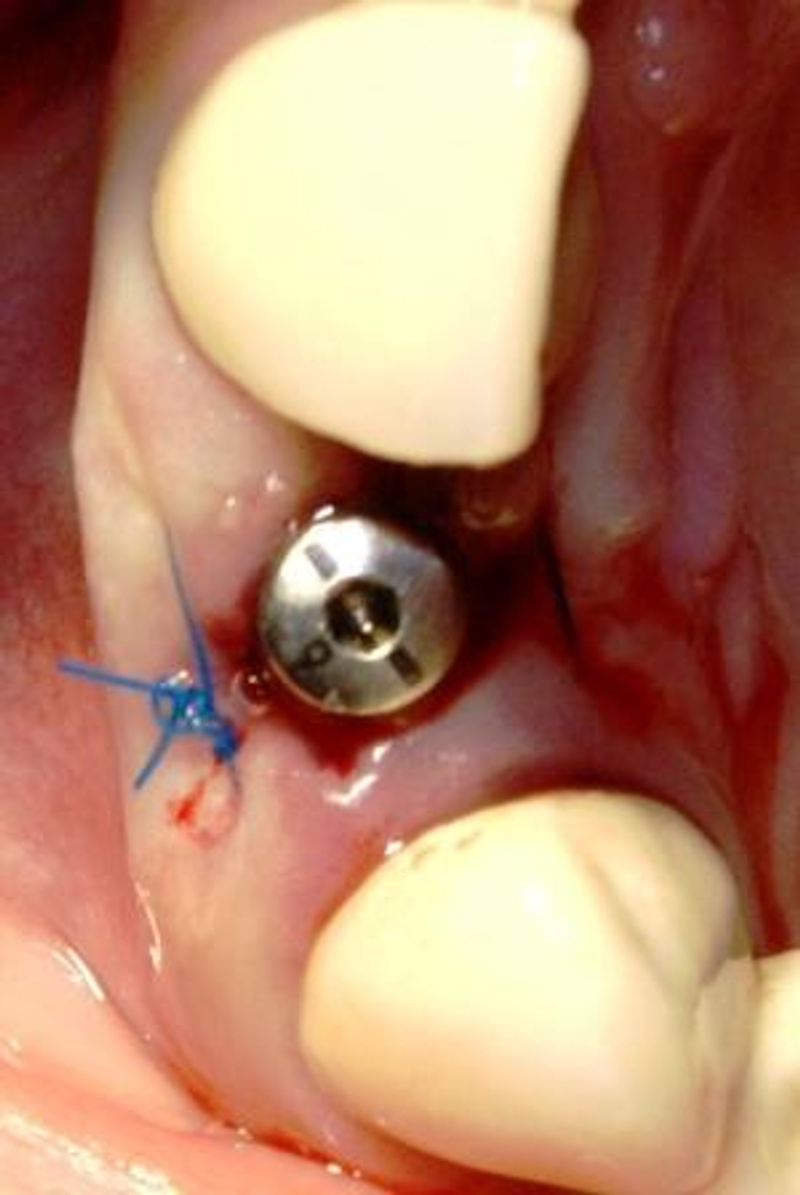

Ну вот и установили имплант, больше боялась. Сама операция прошла быстро, четко, безболезненно, но вот отходняки конечно ужасные у меня

Осталось подождать приживания, одеть коронку, и наконец-то снять брекеты

все дал, дома было все, но пока по пробкам доехали - думала умру, да и у меня все немного сложнее, помимо импланта, наращивали кость, да еще и брекеты стоят - все тянут, в общем жуть